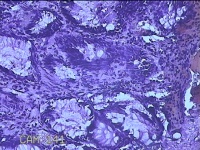

性别

男

年龄

40岁

临床诊断

混合痔

一般病史

反复肛门肿物突出15年。

标本名称

肛门肿物

大体所见

灰白暗红色肿物0.7x0.5x0.2cm一个,表面糜烂。

脱水、透明,浸蜡、脱蜡效果不佳,制片质量差。